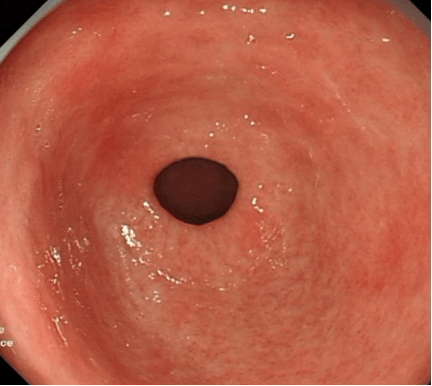

Gastroscopy – View of gastric antrum indicating chronic atrophic gastritis